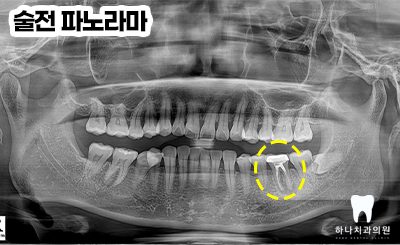

위 환자분께서는 40대 여성분으로

울산삼산동치과 하나치과

홈페이지 블로그를 통해 재신경치료

성공 케이스를 보시고 멀리 북구에서

내원해 주셨습니다.

타 치과에서는 발치를 권유받으셨다고

말씀해 주셨다고 하시며 재신경치료를

받아볼 수 있냐고 여쭤보셨는데요.

우선 치아의 동요도가 없고

염증의 형태가 치근단에 집중되어 있어서

재신경치료를 시도해 보자고 말씀드린 후

진행하기로 하였습니다.

우선 CT 촬영 후 사진에서 보았을 때

원심 근관의 충전을 보면 중앙을

충전물이 지나지 않는 것을

확인할 수 있었습니다.

모든 근관은 치근의 중앙을 지난다는

원칙에 위배되어 하나의 근관이

더 있다는 결론을 도출할 수 있었는데요.